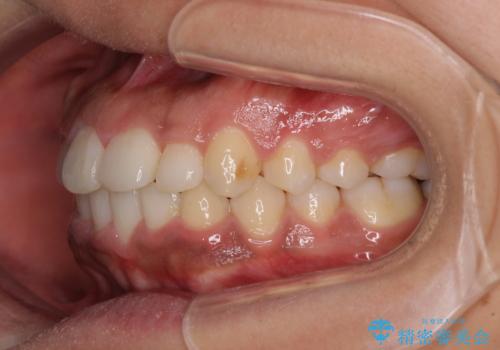

- 上下前歯の叢生を気にして来院された患者様です。

当初はインビザラインにて治療を開始しましたが、自己管理による治療が難しくなり、ワイヤー矯正へ転換して継続しました。

2年ほどインビザライン矯正を続けましたが、終了することができず、ワイヤーへ転換後は1年弱で終えることができました。